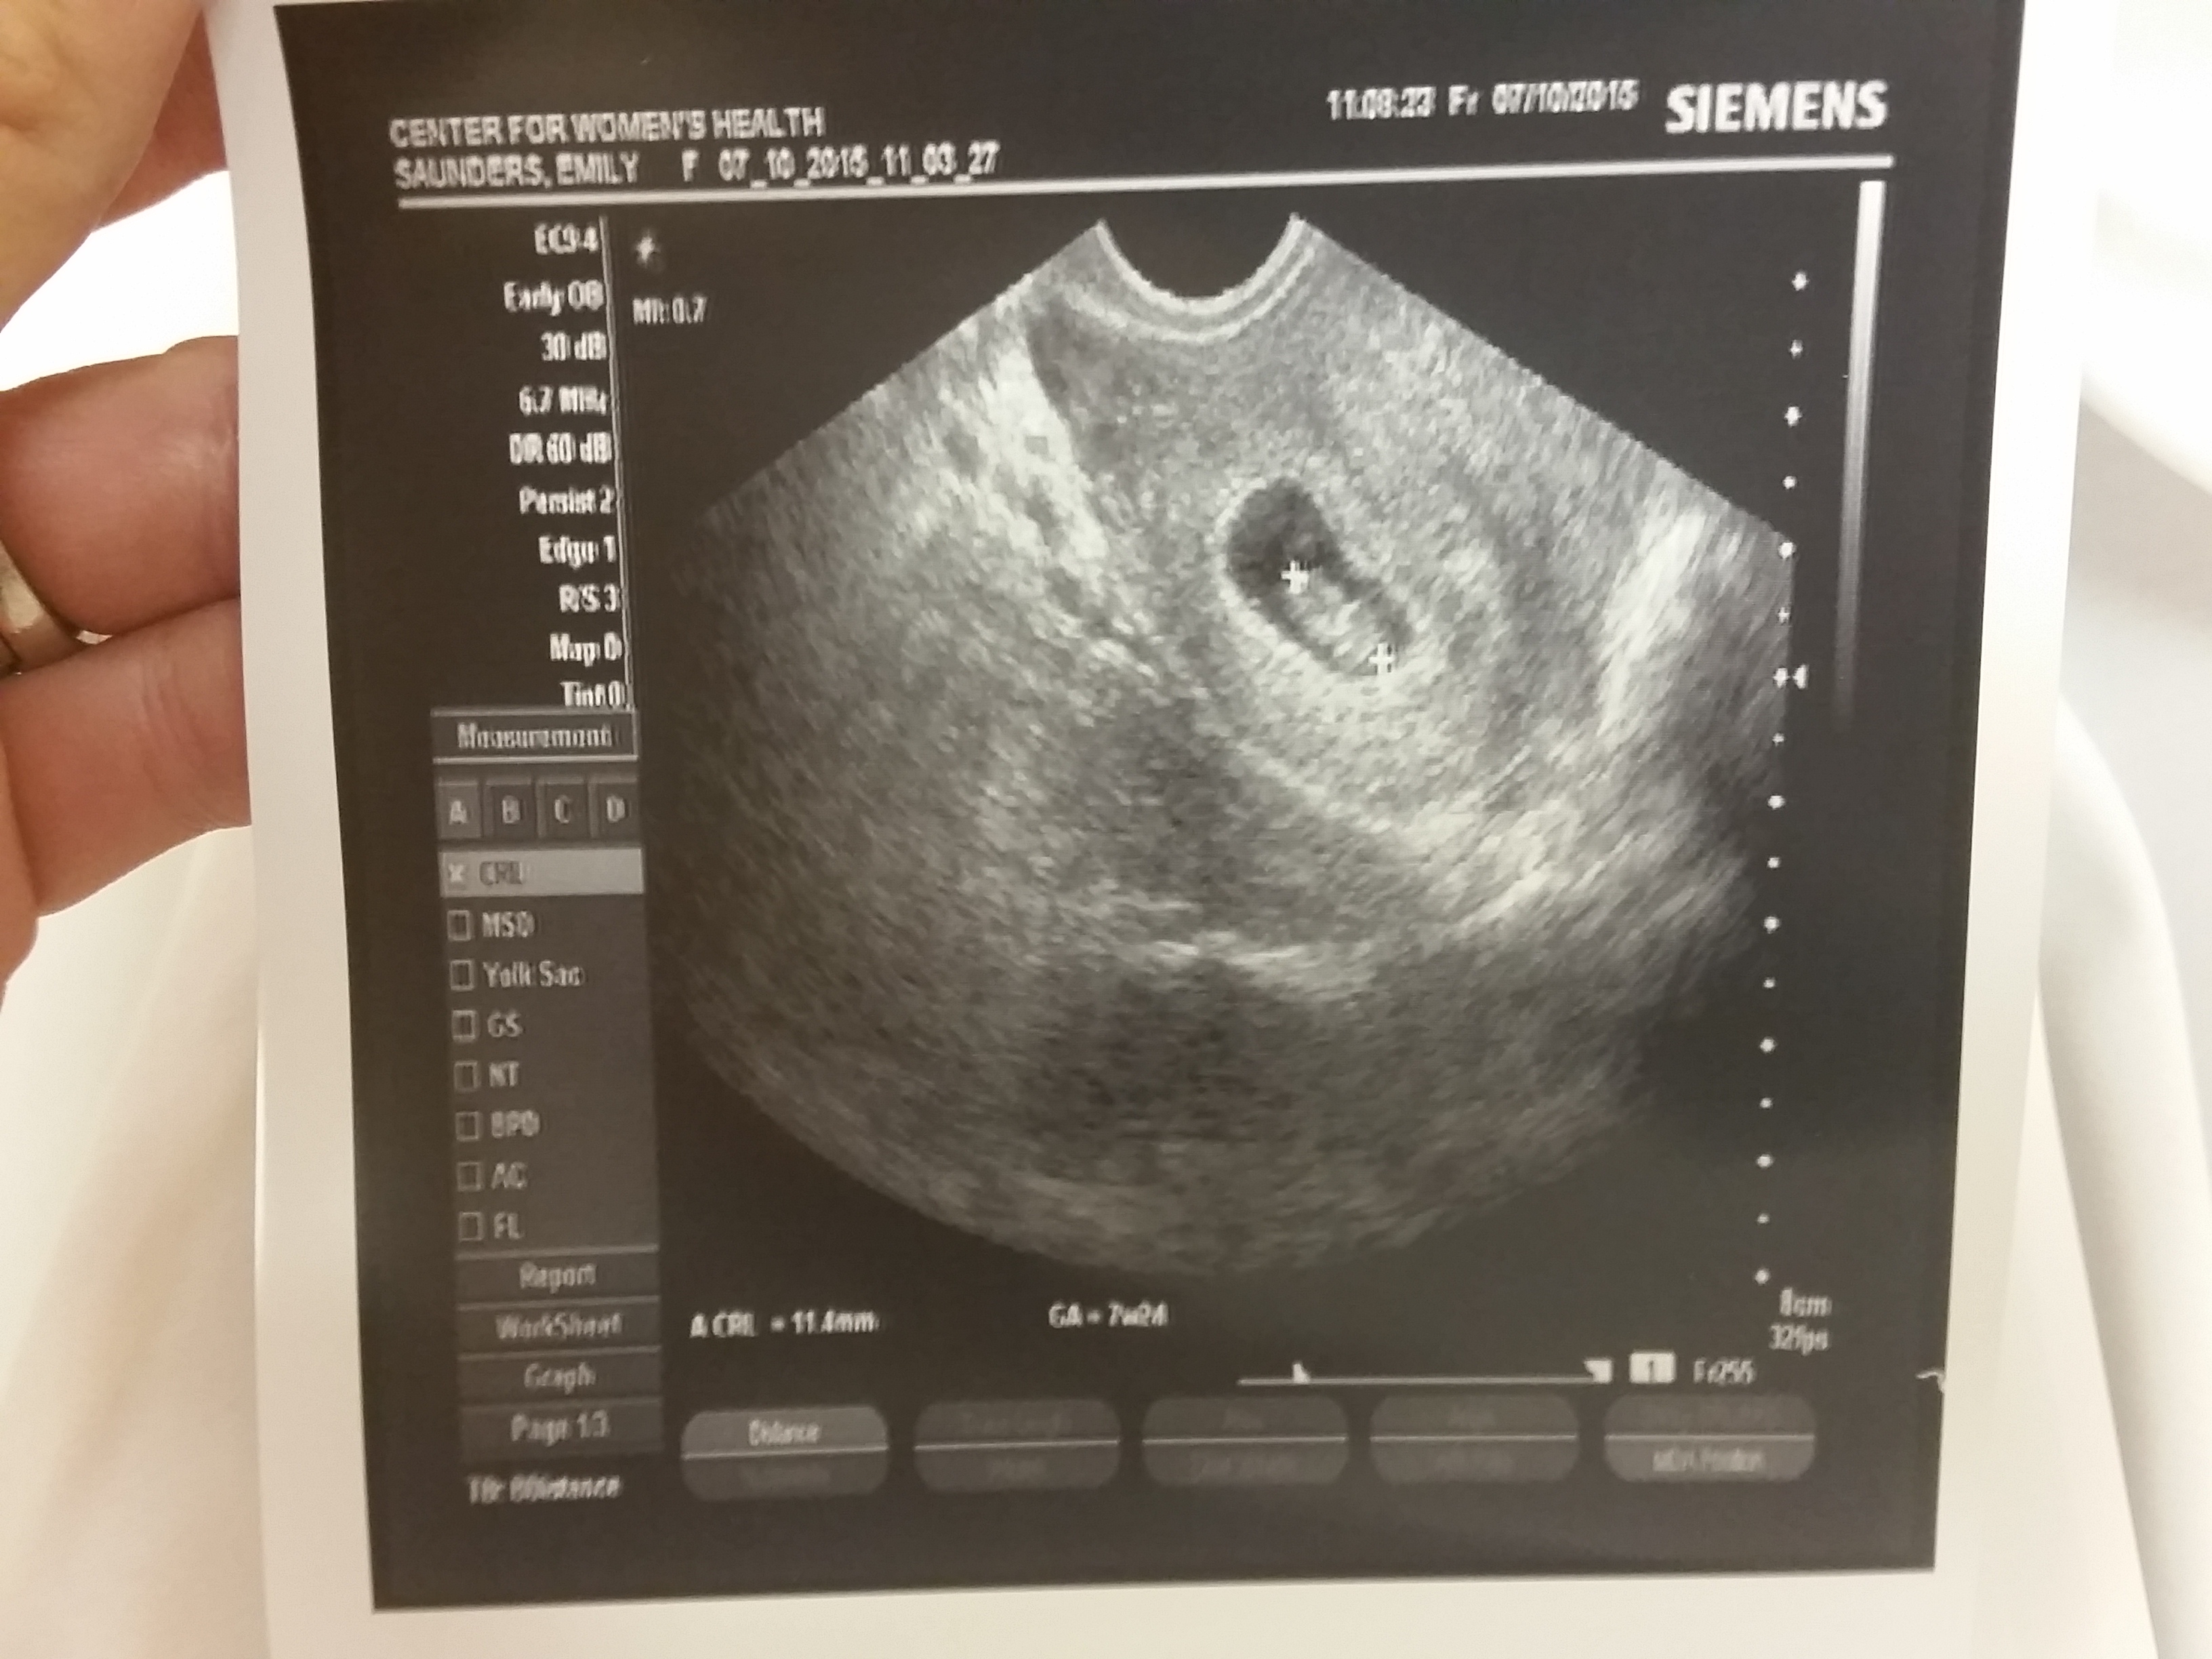

It’s so wonderful to share with you the blessing of pregnancy after loss. I feel overwhelmingly thankful for the opportunity to carry a child so quickly after losing a pregnancy.